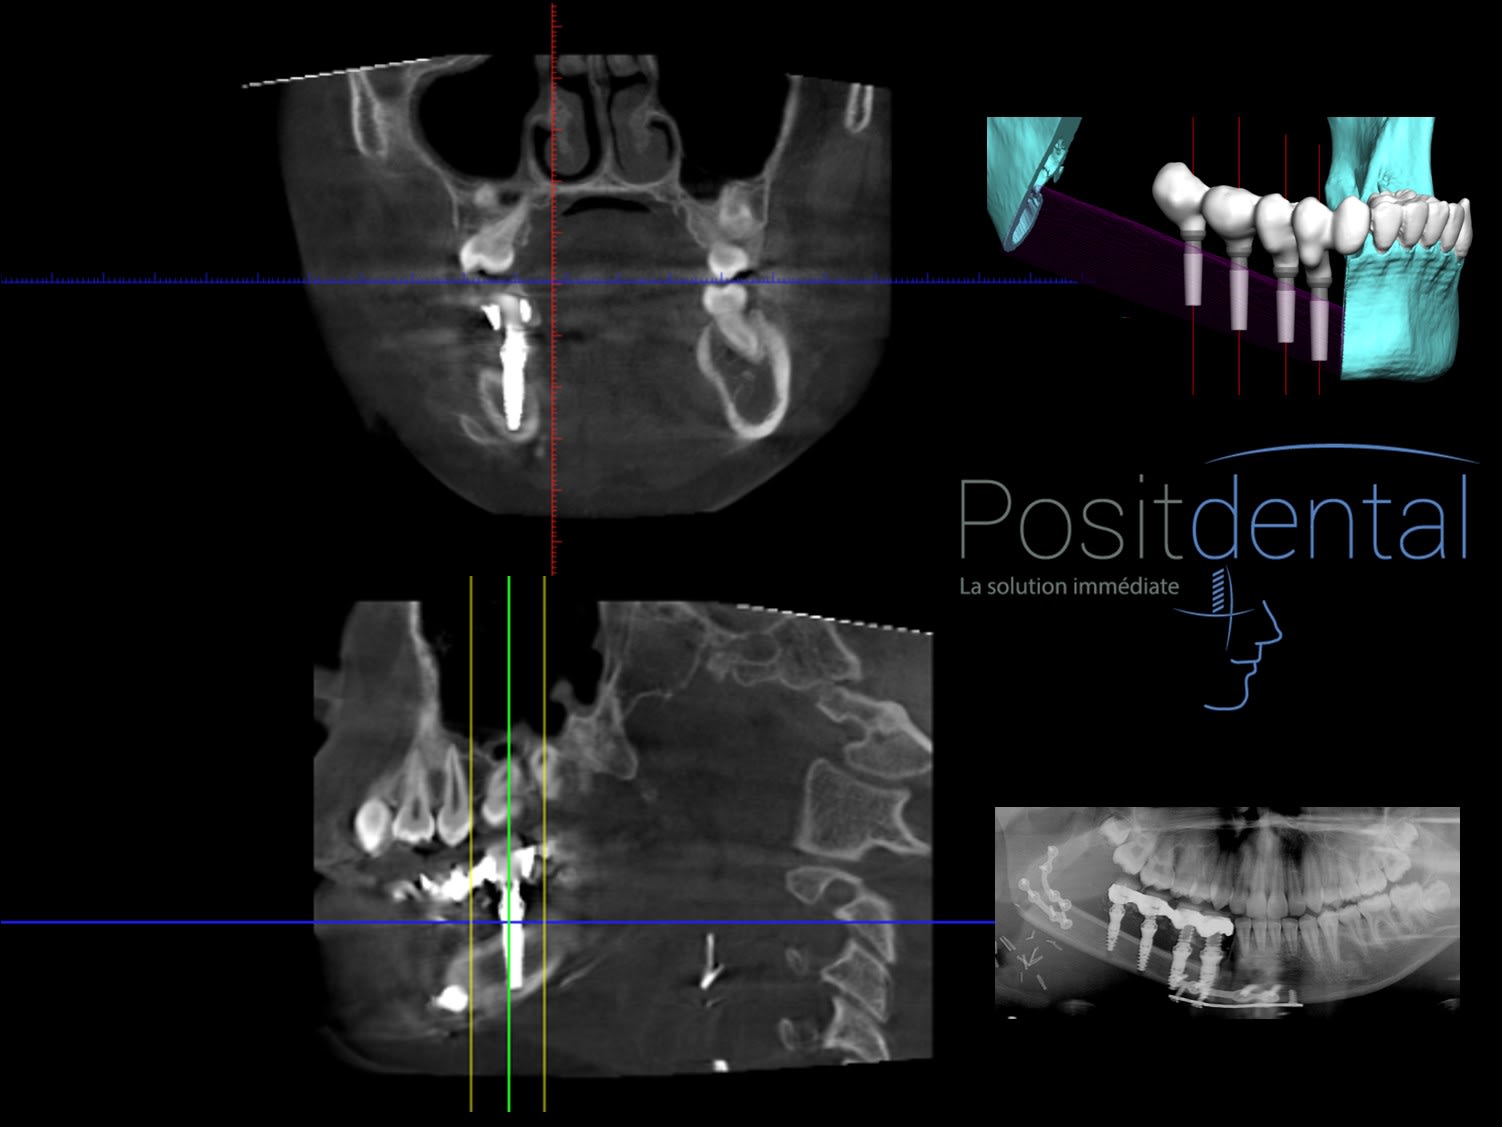

Comment tu expliques la disparition d'éléments anatomique sur cette pano ?

Est-ce que vous pensez que c’est le chirurgien qui s’est raté ? Ou est-ce que c’est le guide de Posit qui est en cause ?

Parce que quand on regarde tout le reste ça a l’air parfaitement adapté (en ce qui concerne la greffe d’os).

04/04/2023 à 08h24

Glenn écrivait:

-----

> Bonjour posit,

> Étant donné que tu as un scan qui date d'un an après la chirurgie, tu pourrais

> montrer des coupes au niveau des implants postérieurs, ce qui permettrait de

> mettre les choses au clair.

> Voir même, rêvons un peu, de clore ce sujet.

J'espère que tu apprécies la perception de l'éclaircissement